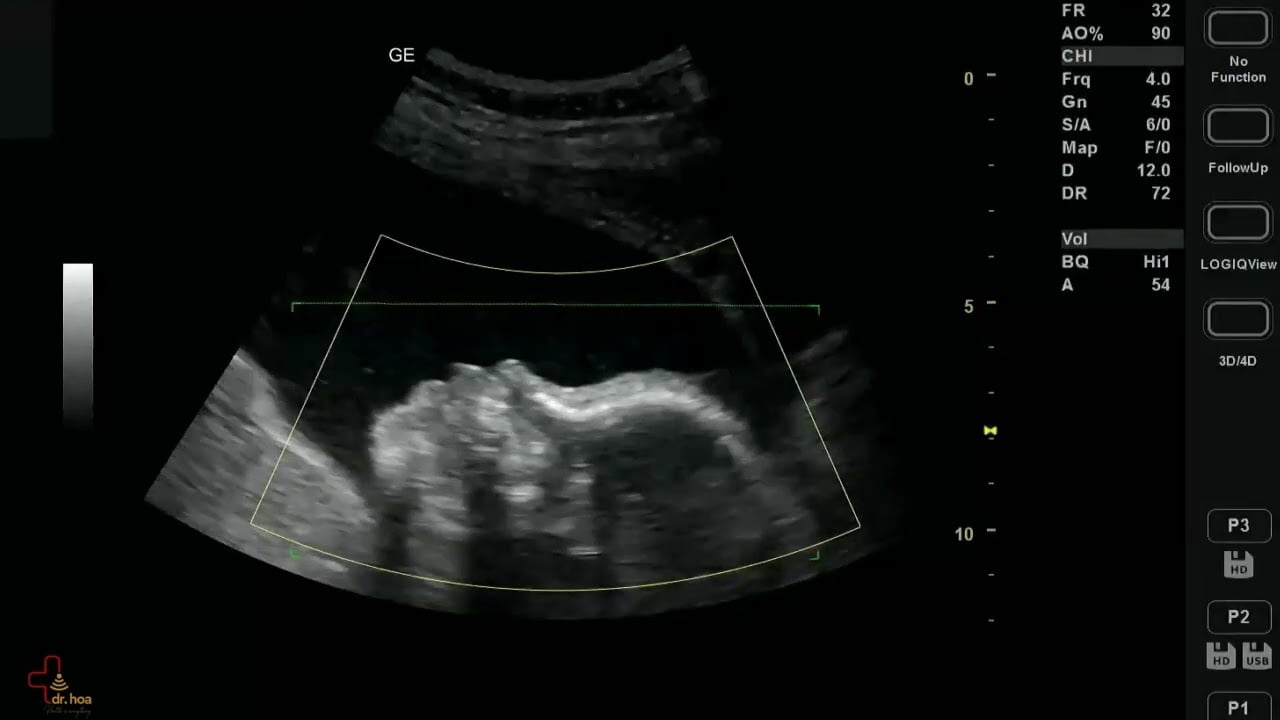

Sieu am Q7 xin gioi thieu Giay phut ngau hung ve Sieu am 4D sieu am thai

Siêu âm Q7 xin giới thiệu “Giây phút ngẫu hứng” về Siêu âm 4D #siêu_âm_thai.